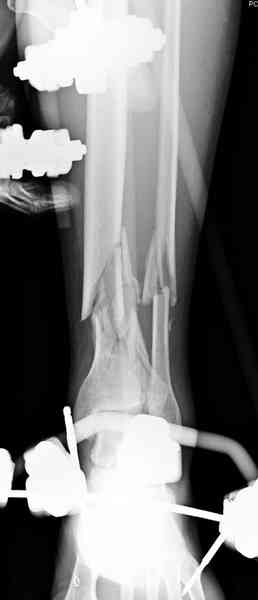

Предыдущей сменой до 4:00 утра по поводу открытого перелома бедра, тибиал плато, пилон и надколенника сделана операция.

На голень наружный фиксатор, рану на бедре ушили (рана была изнутри кнаружи всего 2 см). По протоколу травматических больных, до операции обследован ангиографически, (у больного дистально не смогли определить пульсацию) сосудистый хирург подтвердил проходимость на всем протяжении магистрального сосуда нижней конечности по снимкам ангиограмм.

В настоящее время больной в реанимации по поводу Черепно Мозговой Травмы и состояние улучшается. Запланировал ушивание раны в пятницу, если позволит состояние мягких тканей и при отсутстви отека возможно удастся просунуть перкутанномедиальную пластину.